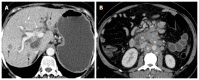

Hilar cholangiocarcinoma is a common malignant tumor of the biliary tree. It has poor prognosis with very low 5-year survival rates. Various imaging modalities are available for detection and staging of the hilar cholangiocarcinoma. Although ultrasonography is the initial investigation of choice, imaging with contrast enhanced computed tomography scan or magnetic resonance imaging is needed prior to management. Surgery is curative wherever possible. Radiological interventions play a role in operable patients in the form of biliary drainage and/or portal vein embolization. In inoperable cases, palliative interventions include biliary drainage, biliary stenting and intra-biliary palliative treatment techniques. Complete knowledge of application of various imaging modalities available and about the possible radiological interventions is important for a radiologist to play a critical role in appropriate management of such patients.We review the various imaging techniques and appearances of hilar cholangiocarcinoma and the possible radiological interventions.